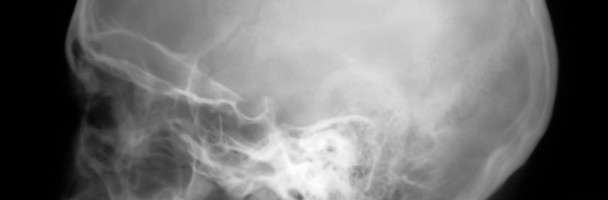

La teleradiografia cefalometrica è un esame breve e non doloroso richiesto dai dentisti per valutare le diverse anomalie di costituzione, sviluppo e posizione dei denti e delle ossa mascellari allo scopo di prevenire, eliminare o ridurre tali anomalie cercando di riportare o di mantenere gli organi deputati alla masticazione e il profilo facciale nella loro posizione più corretta possibile.

Nella radiografia devono essere rappresentati nel modo migliore possibile quei punti e quelle strutture ossee che poi il medico dentista deve poter riconoscere per tracciare in modo preciso le linee del tracciato cefalometrico. E’ quindi necessario conoscere l’esatta localizzazione dei punti impiegati in cefalometria e delle strutture anatomiche che essi definiscono.

La teleradiografia può essere eseguita in tre proiezioni: latero-laterale, postero-anteriore ed assiale. La più usata nella diagnosi cefalometrica è la latero-laterale.